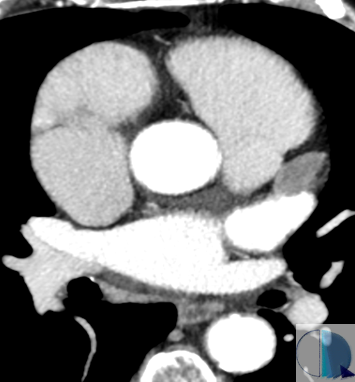

Hey there! Let´s get some #YesSpectralCCT for this friday at RM y TC Rosario. This is the case of a 53yo patient who underwent a body CT for follow-up of colon cancer and unknown atrial fibrillation. The study was unremarkable, except for this finding. 1/8

Hey there! Let´s get some #YesSpectralCCT for this friday at <a href="/RMyTC_Rosario/">RM y TC Rosario</a>. This is the case of a 53yo patient who underwent a body CT for follow-up of colon cancer and unknown atrial fibrillation. The study was unremarkable, except for this finding.

1/8

ANGIO TAC CARDÍACO PEDIÁTRICO🫀👶🏻 Realizado a paciente de menos de un año de edad. Se le administró contraste yodado para la realización de este estudio. Seguro, preciso y sencillo.